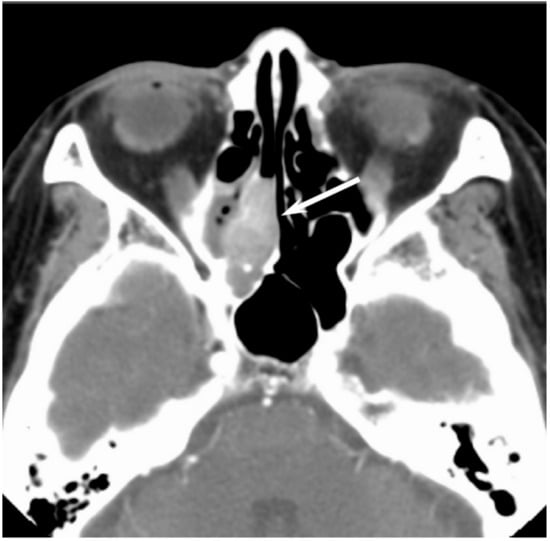

Figure 5. Diffuse large B-cell lymphoma of the left maxillary sinus. Contrast-enhanced CT image showing a homogeneously enhanced lesion accompanied by remaining sinus walls as a linear structure within the tumor (arrows).

On CT, sinonasal lymphomas frequently show both infiltrative or permeative bony invasion and exhibit varying degrees of regional bony destruction [12]. NHLs with permeative-type tumor invasion typically cross the sinus wall and exhibit remnants of sinus wall as a linear structure within the tumor (Figure 5) [24]. In contrast, bony resorption or remodeling caused by the lymphoma may also be accompanied by bone sclerosis [25]. NHLs usually show isointensity on T1WI and slightly hyperintensity on T2WI [11]. Although the signal intensity of NHLs is nonspecific, the ADC measurement helps differentiate these tumors from other malignancies. In the maxillary sinus, the ADC values of NHL (0.61 × 10−3 mm2/s) were shown to be lower than those of SCCs (0.95 × 10−3 mm2/s), which reflects the greater cellularity of NHLs [12]. Although NHLs usually appear as a homogeneously enhanced mass, necrotic areas within the tumor are occasionally observed in NK/T-cell lymphoma [26,27].